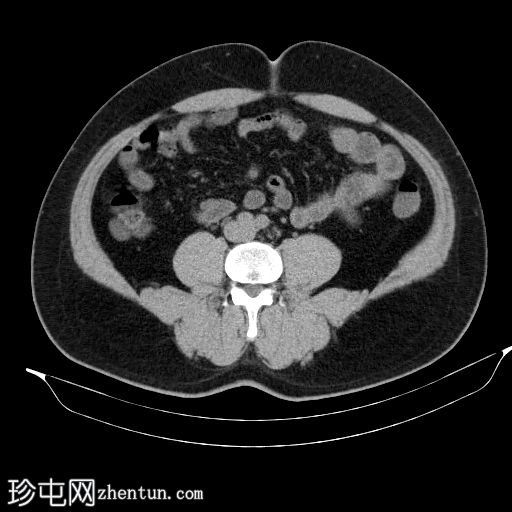

轴位

平扫

左侧肾盂输尿管连接部(PUJ)可见一枚较大的不透射线结石,最大直径达24 mm,平均CT值约为1160 HU。该结石引起反压改变,导致明显的左肾积水。

此外,左肾中极肾盏内可见一枚直径约13 mm的非梗阻性不透射线结石,平均CT值为1100 HU。

另外,左肾下极肾盏内可见多枚聚集性不透射线结石,总直径约20 mm,平均CT值约为1140 HU。

偶然发现的异常包括前列腺内多发粗大钙化灶,主要位于尿道周围,并伴有轻度肝肿大。